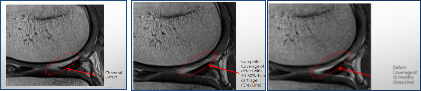

這是細胞因子UCF膝關節退行性病變治療之前,之後6個月,和之後12個月的MRI照片,可以清醒看到膝關節軟組織的增厚,修復的變化過程。

修復效果: 治療後一個月反饋,疼痛基本消失,可擺脫輪椅獨立行走。 治療後三個月反饋,無疼痛感,生活恢復正常,行走正常。至今已一年多關節疼痛消失無復發。通過MRI影像對比可見老人的膝關節骨密度明顯改善提高。